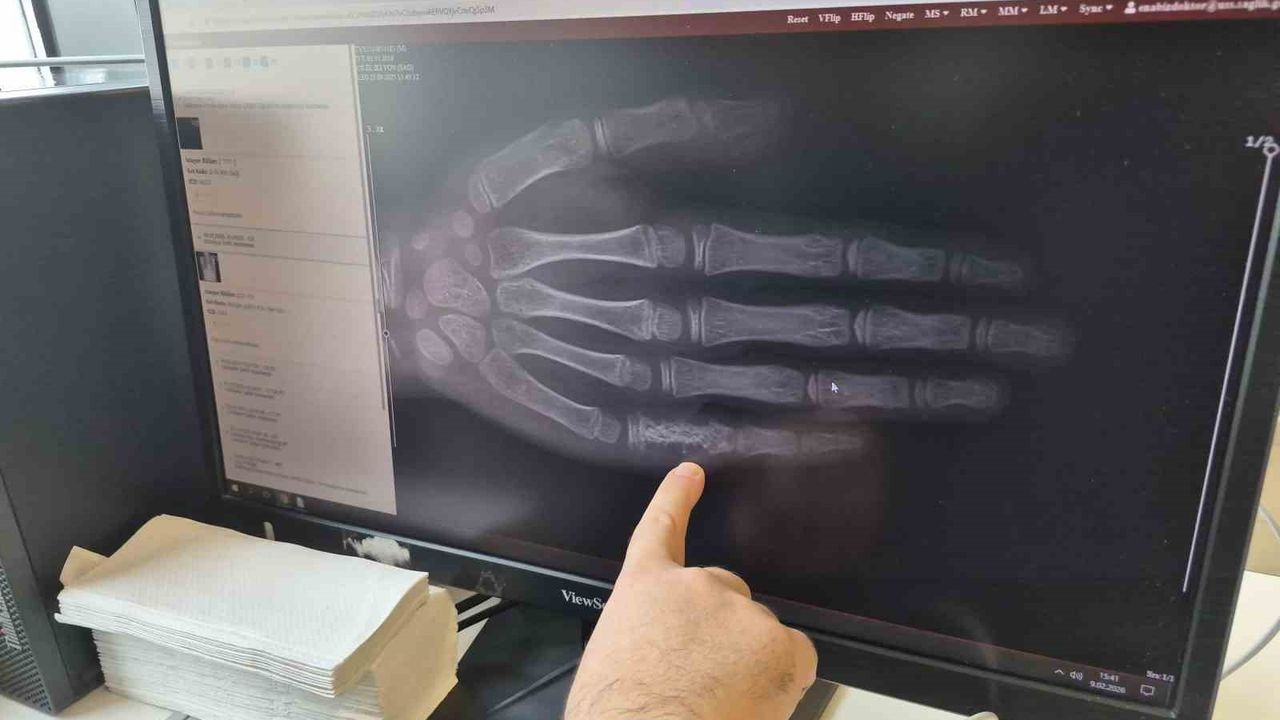

Doç. Dr. Ersin Töret, 15 Şubat Çocukluk Çağı Kanser Günü kapsamında bilgilendirmede bulundu. İstatistiklere göre her 100 hastadan birinin kanser olduğunu söyleyen Dr. Töret, bu vakalar arasında çocukluk çağı kanserinin de görüldüğünü ifade etti. Eskişehir'de her ay 5 ila 7 arasında çocuğun kanser tanısı aldığını belirten Töret; bu vakaların büyük bölümünü lösemi olarak bilinen kan kanserinin oluşturduğunu, ikinci sırada beyin tümörleri ve üçüncü sırada ise lenf bezi kanserlerinin yer aldığını dile getirdi.

Konuyla ilgili açıklamada bulunan Çocuk Hematoloji ve Onkoloji Doç. Dr. Ersin Töret, 'Bu kanserlerde genelde ailelerimiz açısından farkındalık oluşturmak önemli. Erken tanı hastalığın tedavi sürecinin daha kısa sürede tamamlanmasını sağlarken, yaşamda kalma şansını daha da artırmaktadır. Hastalarımızda özellikle 3 günden daha süren uzun ateş olması, kemik eklem ağrıları olması, ailenin çocuklarına banyo yaptırırken veya kıyafetlerini değiştirirken ellerine sert kitleler gelmesi dikkat edilmesi gereken belirtilerdir. Ayrıca keyifsizlikleri, oyun oynamaya karşı isteksizlikleri varsa, çocuk rutin olarak ilgilendiği uğraşlarını yapamıyorsa doktor tarafından değerlendirilmesinde fayda var' şeklinde konuştu.

Eskişehir Şehir Hastanesi'nde hem hastalığın tanısı için gerekli tetkiklerin hem cerrahi işlemlerin yapıldığını vurgulayan Dr. Töret, 'Pek çok kanseri burada hastanemiz çatısı altında tedavi edebilmekteyiz. Çocukluk çağı kanseri de buna dahil. Çocukluk çağı kanserleri genellikle biraz kötü piyango gibidir. Özellikle ilk 5 yaşta görülüyor. Kökeni erken dönem hücresel gelişime dayanan bazı lösemi türleri ilk 5 yaşta daha sık görülmektedir' ifadelerini kullandı.